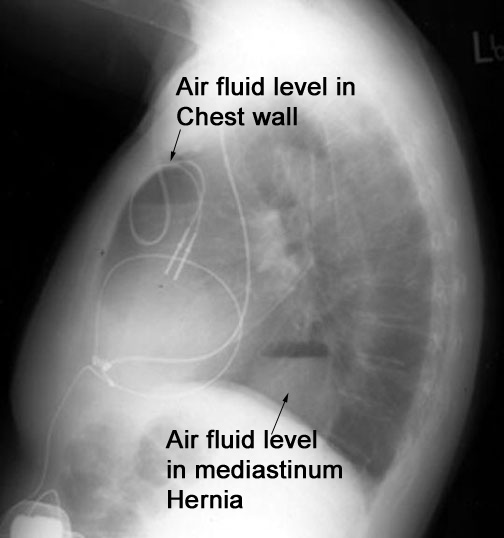

Case 6

Lateral

Labeled Image

What is the differential for air fluid levels in the mediastinum?